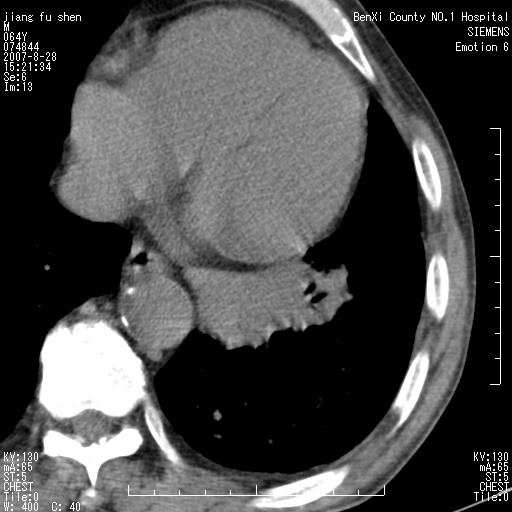

男、64、咳嗽、发烧一周、左肺呼吸音稍弱。既往肺结核,右手结核。

本次扫描患者未带原片,左肺下叶发现病灶。左肺上叶空洞,5组淋巴结肿大,1cm左右。

平扫20-33hu

增强31-33hu

1分半44-52

2分55-67

左肺下叶前内基底段支气管明显偏心性狭窄,周围分叶状肿块,伴有阻塞性肺炎,支持肺癌可能性大。

考虑左肺中央型肺癌并阻塞性肺炎

病灶边缘可见多量较长棘影及纤维条索状影,除外病灶边缘较光整,病灶有分叶表现,但多表现为较浅分叶,且向周围伸出之叶多呈尖角改变,且边缘较光整,病灶增强呈中度延时增强,且早期及中期仅轻度增强,结合患者病史,多考虑继发型肺结核,炎性增殖灶形成,不除外肺癌